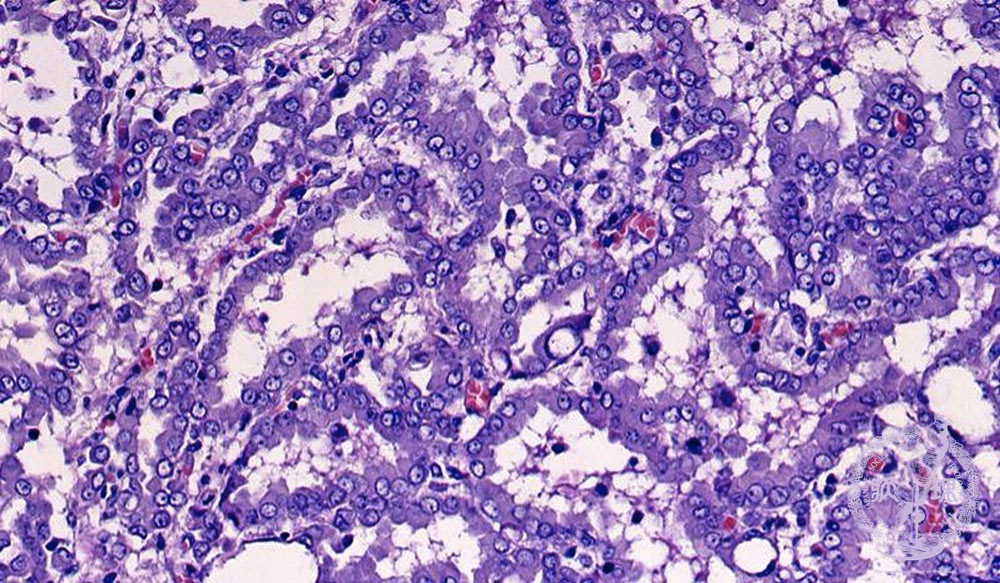

Microscopic view (HE stain, high power view): Mesothelioma cells have round nuclei and eosinophilic cytoplasm. Differentiation from lung adenocarcinoma is sometimes difficult.